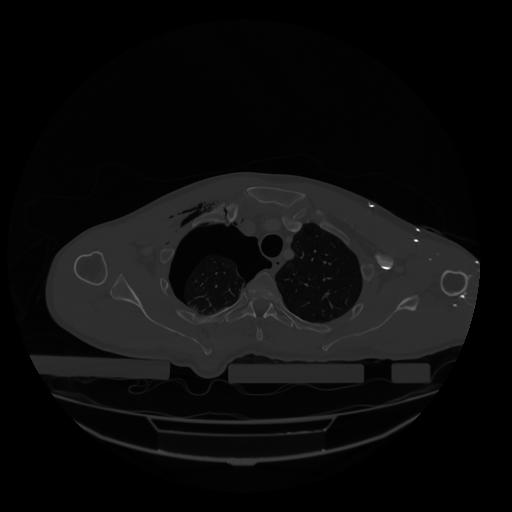

28 CUERPO,CE,Vol,2.0,CUERPO,,